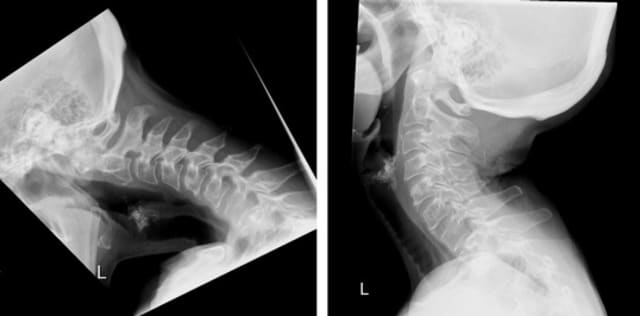

Mittels einer neuartigen chirurgischen Technik konnte eine Patientin mit Dropped Head Syndrom erfolgreich ohne Versteifung behandelt werden. Die Operationsmethode wurde am Universitären Wirbelsäulenzentrum Zürich entwickelt.